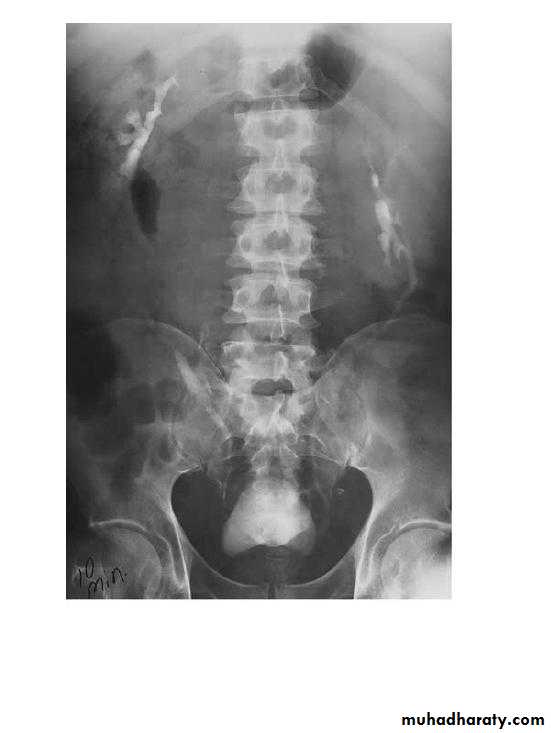

Pelvi-ureteric junction obstructionFilling defects